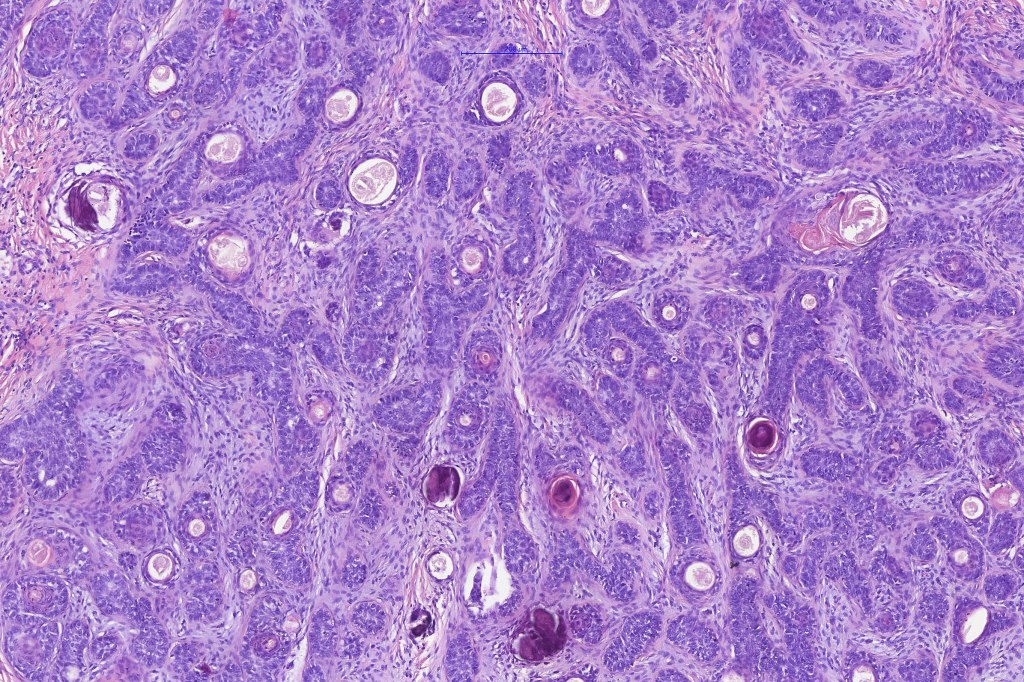

•Variable keratin cysts

•Sebaceous & glandular differentiation

•Cribriform and palisaded (rippled) pattern

•Trichogerminoma (see images)